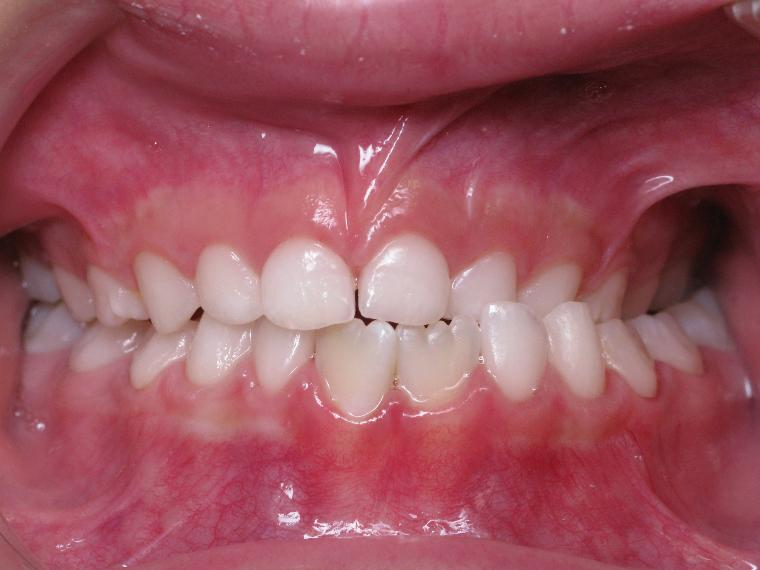

bilan début et fin de traitement